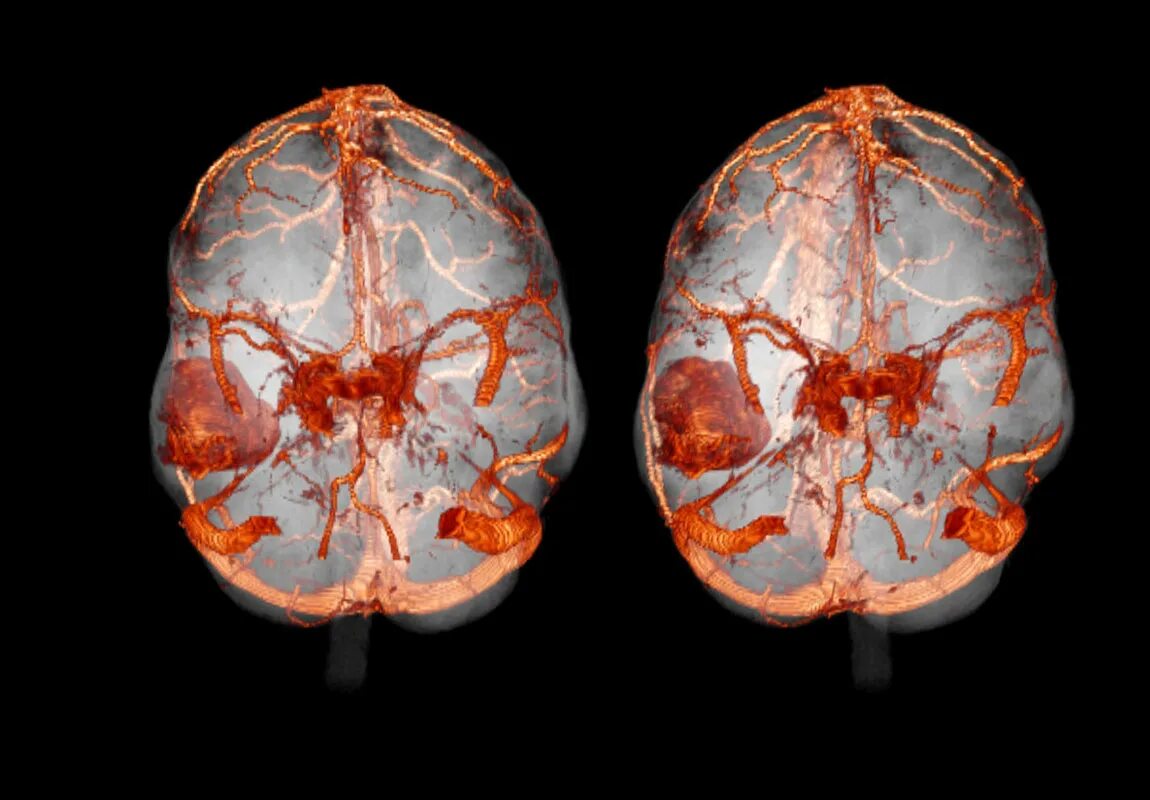

Мрт с контрастированием головного